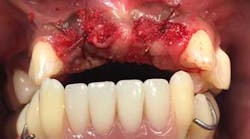

Upon returning for the above tooth removal, tooth No. 5 self-avulsed and the other teeth were removed and a temporary partial placed (figures 4 and 5).

Approximately, two-and-a-half years into active periodontal treatment and maintenance therapy, the patient and the authors discussed removal of all remaining teeth and rehabilitation of the mouth with the All-On-4 (AO4) approach (figure 6).